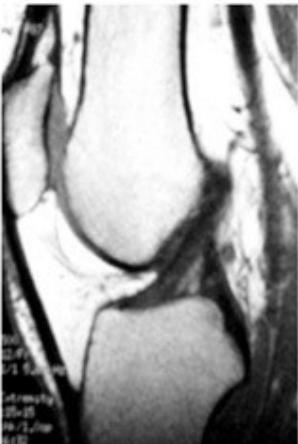

MRI (Gold Standard)

- Best imaging modality for ACL injuries

MRI Findings:

- Normal ACL

- Torn ACL